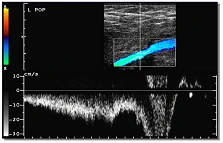

Der sensitive Spektraldoppler liefert eindeutige Ergebnisse. Im Beispiel: Funktionsdiagnostik der Vena poplitea (Kniekehlenvene)